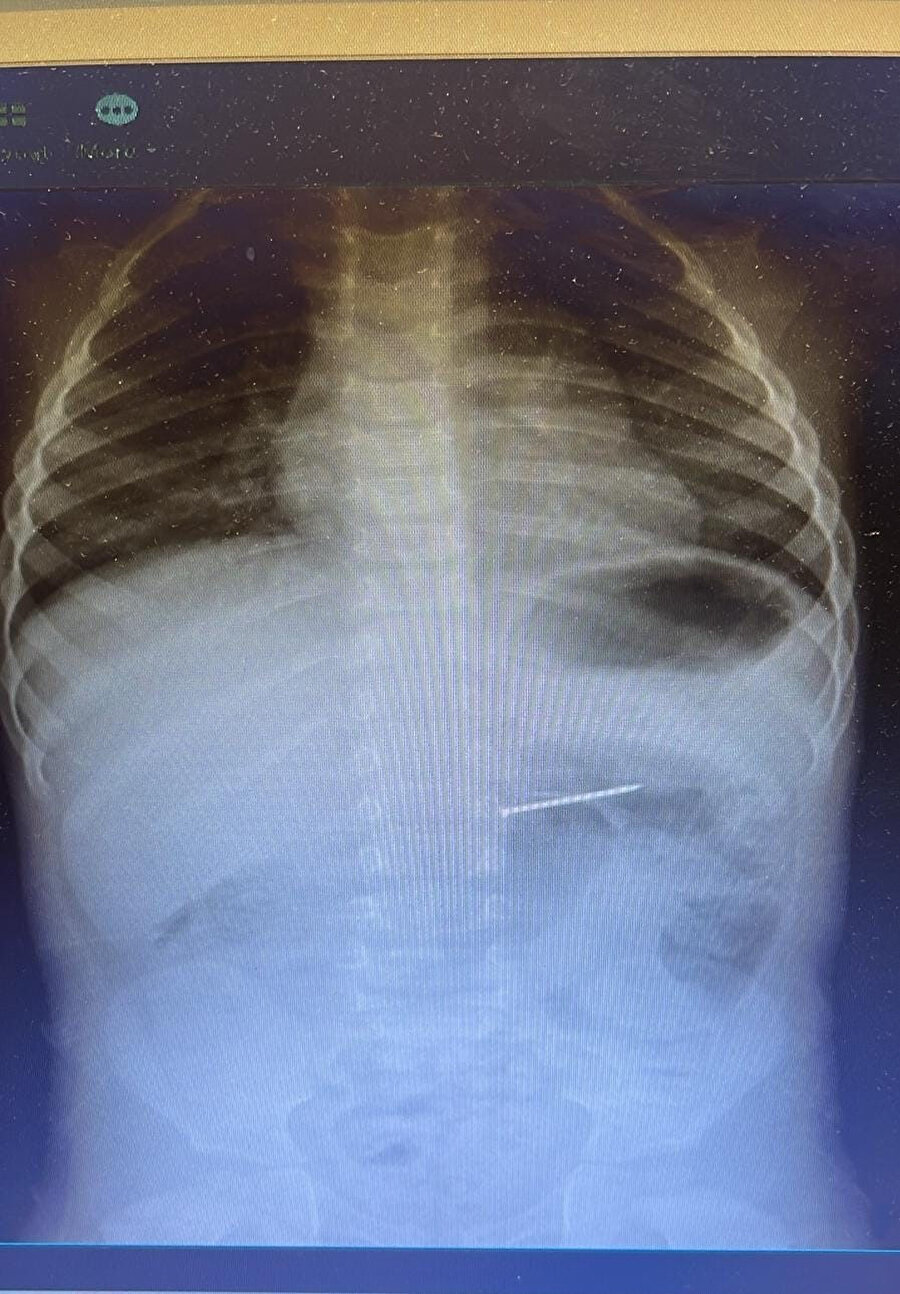

Burdur’un Bucak ilçesinde yaşayan 2 yaşındaki bir çocuk, yuttuğu çivi nedeniyle ailesi tarafından acil sağlık ekiplerine bildirildi. 112 Acil Servis aracılığıyla Süleyman Demirel Üniversitesi (SDÜ) Hastanesi’ne sevk edilen çocuk, Çocuk Gastroenteroloji ve Endoskopi Birimi’nde değerlendirmeye alındı. Radyolojik inceleme sonucu yaklaşık 4 santimetre uzunluğundaki çivinin midedeki konumu tespit edildi ve hemen endoskopik müdahale yapıldı. Yapılan işlemle çivi, herhangi bir komplikasyona yol açmadan başarılı şekilde çıkarıldı. Hasta, kısa süreli gözlem amacıyla serviste takip altına alındı ve sağlık durumu stabil şekilde taburcu edildi.